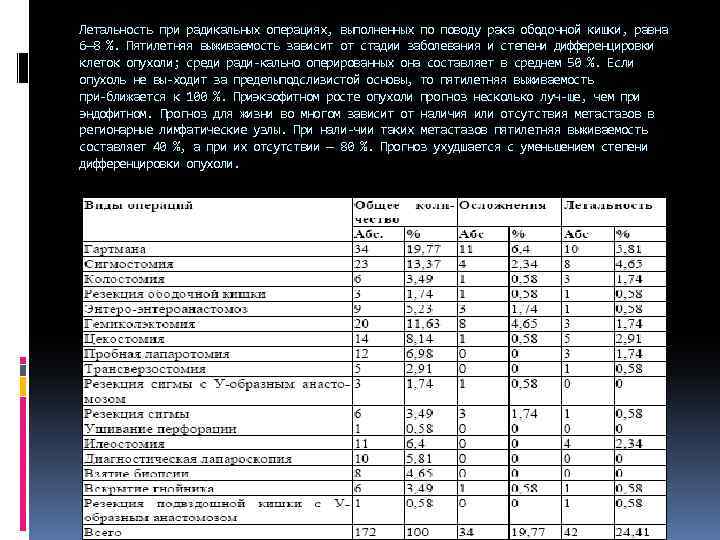

Летальность при радикальных операциях, выполненных по поводу рака ободочной кишки, равна 6— 8 %. Пятилетняя выживаемость зависит от стадии заболевания и степени дифференцировки клеток опухоли; среди ради кально оперированных она составляет в среднем 50 %. Если опухоль не вы ходит за пределыподслизистой основы, то пятилетняя выживаемость при ближается к 100 %. Приэкзофитном росте опухоли прогноз несколько луч ше, чем при эндофитном. Прогноз для жизни во многом зависит от наличия или отсутствия метастазов в регионарные лимфатические узлы. При нали чии таких метастазов пятилетняя выживаемость составляет 40 %, а при их отсутствии — 80 %. Прогноз ухудшается с уменьшением степени дифференцировки опухоли.